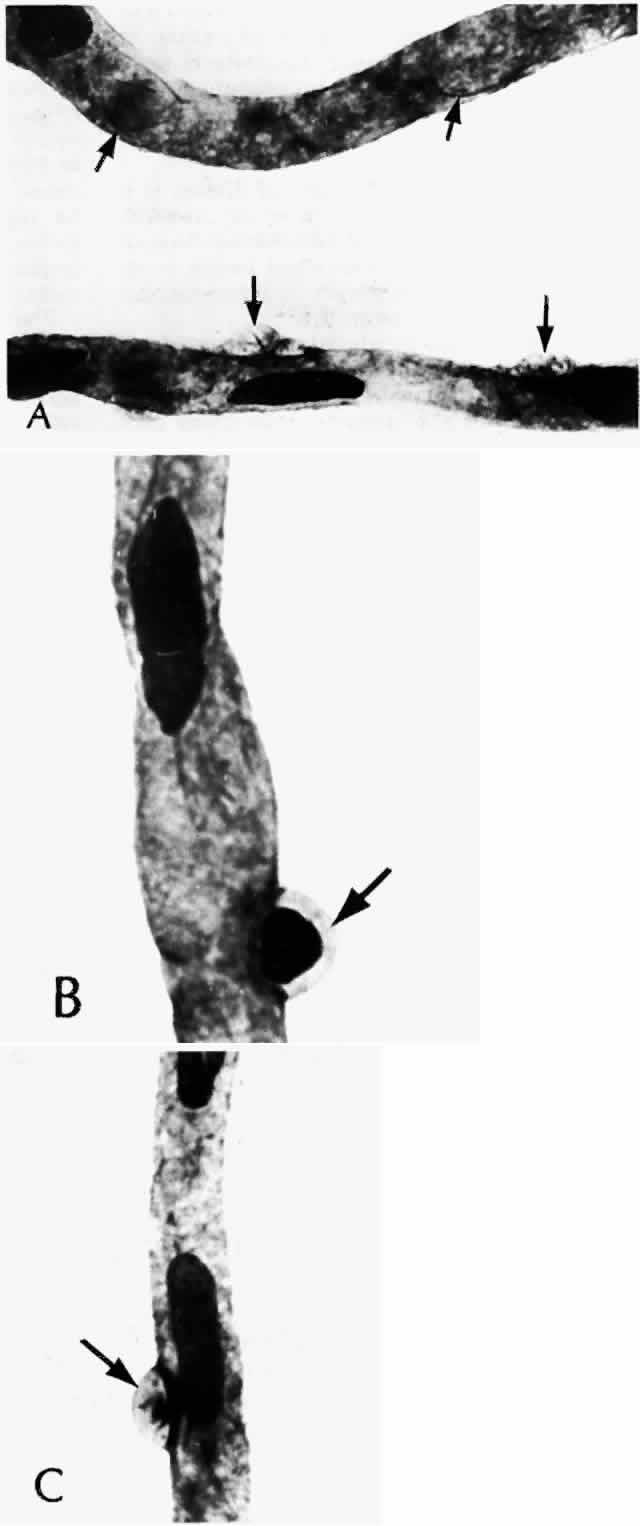

As shown by trypsin digestion, capillary pericytes are lost first,27 followed by endothelial cells (Figs. 6 and 7). Aldose reductase, one of the enzymes in the sorbitol metabolic pathway, is present in significant quantities in retinal capillary pericytes, but not in endothelial cells, and may thus be implicated in the formation of microaneurysms.37 The final result is an acellular segment of capillary that is nonperfused on fluorescein angiography.36

Fig. 6. Diabetic retinal capillary. A. Basement membrane shell (arrows) is the only remaining indication of where the pericytes had been. B. Nondiabetic normal capillary shows the basement membrane shell (arrow) around the pericyte. C. Diabetic capillary has only a basement membrane shell (arrow), with the nucleus absent. (A, PAS, × 630; B, PAS, × 850; C, PAS, × 630)

The retinal veins can also become irregular and tortuous with sausage-shaped dilatations. The vascular walls become diffusely permeable so that they both leak and stain with fluorescein. These changes also seem to be associated with ischemia. As shown by trypsin digestion, the beaded areas are hypercellular (Fig. 10).43 Diabetes is also a risk factor for branch retinal vein occlusion47 and central vein occlusion.43

Fig. 10. A and B. Sausage-shaped venules (arrows) result from irregularities in the venular walls. Note the arteriolar-venular connections and thickened capillary basement membranes (dark-colored capillaries). Retinal capillary microaneurysms tend to arise from cellular (viable) capillaries and cluster around acellular (nonviable) capillaries. The venular walls not only are irregular, but they also have an unusual presence of saccular microaneurysms (Inset 1, and Inset 3 from the area of the double arrows). Inset 2. Fundus appearance of microaneurysms, a cotton-wool spot, irregular venules, and intraretinal neovascularization in the form of a rete mirabile. (a = arteriole; v = venule) (A and B, PAS, × 16; Inset 1, PAS, × 40; Inset 2, fundus; Inset 3, PAS × 54)

Other capillary changes, more severe and extensive than microaneurysms, are collectively termed intraretinal microvascular abnormalities (IRMAs). Clinically, these manifest as dilated channels that leak fluorescein and show vascular wall staining (Fig. 11). De Venecia and co-workers36 were able to distinguish between IRMAs arising from arteriolar capillaries and IRMAs arising from venular capillaries. The IRMAs associated with arterioles exhibited early filling and late leakage on angiography. Histologically, they appeared as solid proliferations of endothelial cells, adjacent to acellular capillaries. In some instances, they may represent true intraretinal neovascularization. The IRMAs adjacent to venules filled in the early venous phase and leaked late. Histologically, they were irregularly dilated, had thin walls, and may have represented shunts.

Fig. 11. Arteriolar-venular connection (collateral) consists of a dilated cellular capillary (arrow) with an increased number of anuclear (apparently nonviable) capillaries. (PAS, × 16)